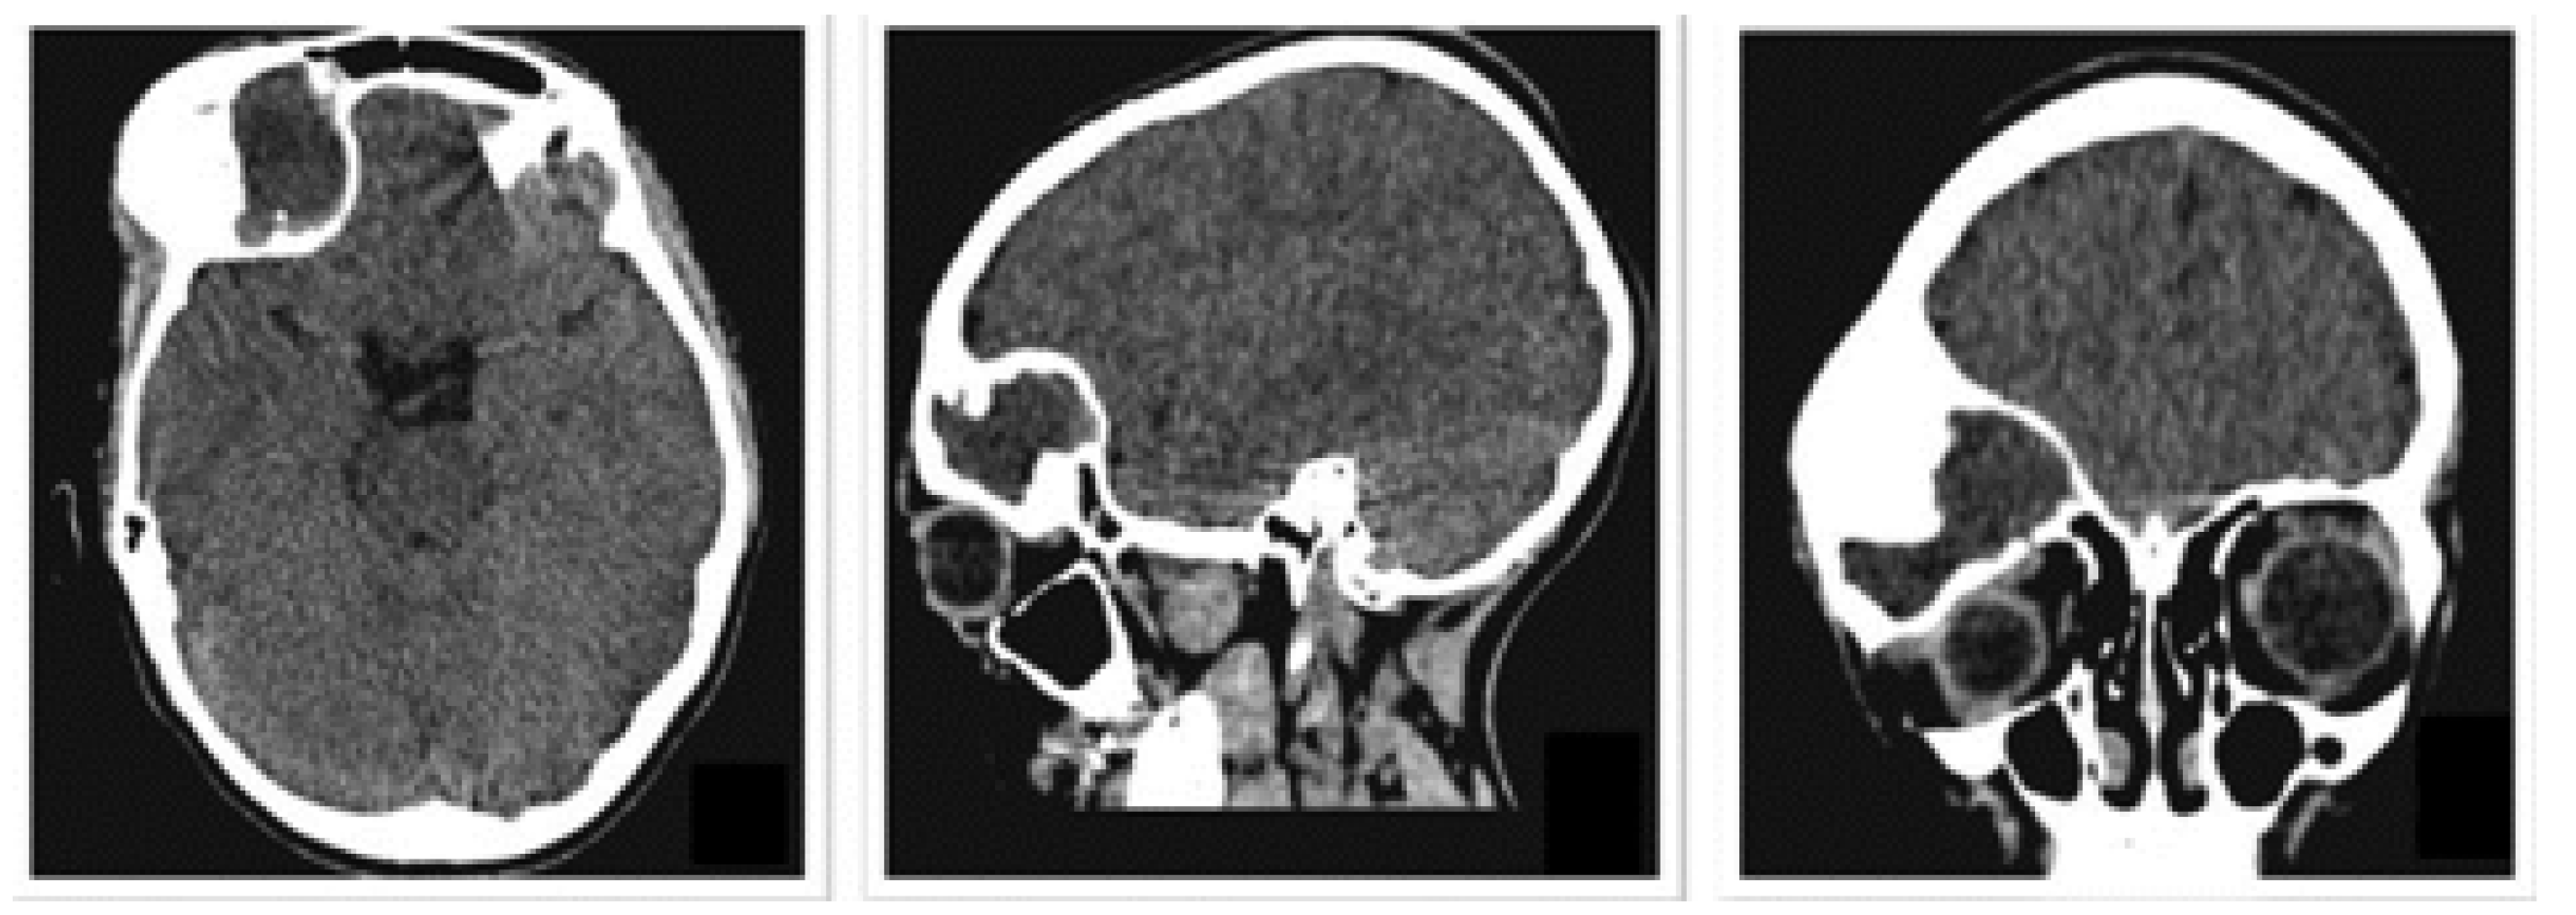

3.2.1. Diagnosis and Analysis

3.2.2. Surgical Planning

3.2.5. Post-Operative Results